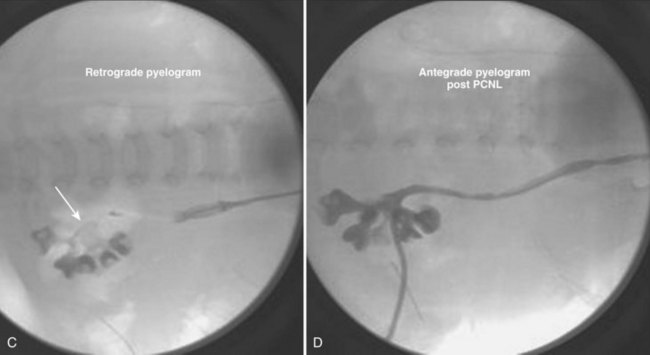

Much planning is required prior to embarking on PCNL in children. Films must first be reviewed scrupulously to determine if the stone(s) is/are amenable to a percutaneous procedure. Nephrocalcinosis in children, for example, may be confused with staghorn calculi; the etiology and treatment are very different (Fig. 135–8). Infection is the most common causative agent in the formation of a staghorn calculus, and PCNL is a first-line therapy. The most frequent causes of nephrocalcinosis are hereditary tubulopathies and vitamin D intoxication (Ammenti et al, 2009). Medullary sponge kidney is a renal malformation characterized by cystic anomalies of precalyceal ducts, which is frequently associated with nephrocalcinosis and stone formation (Gambaro et al, 2006). Nephrocalcinosis is most often not amenable to successful endourologic treatment(s) because calculi are intraparenchymal and thus outside the collecting system. Management is often medical and aimed at prevention of further nephrocalculi, a cause of worsening renal function.

Figure 135–8 A 9-year-old boy with cerebral palsy and gross hematuria. CT scan demonstrated bilateral nephrolithiasis (A) thought to be staghorn calculi. Plain radiograph (B) and bilateral retrograde pyelograms (C and D) correlate to show nephrocalcinosis (white circles and white arrows, respectively) reflective of medullary sponge kidney disease. Subsequent metabolic workup revealed renal tubular acidosis (RTA) with hypercalciuria.